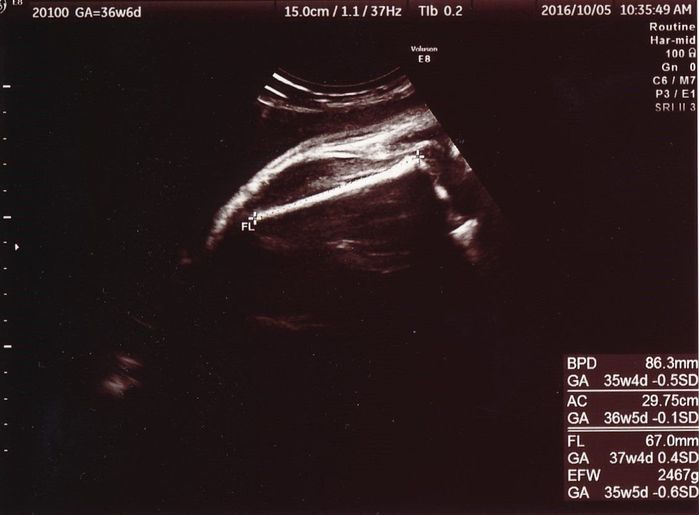

妊娠36週目のエコー写真

これが最後の写真です。大腿骨の長さから推定される体重は2467gと、かなり大きくなりました。貧血もこの頃にようやく落ち着きを見せ、あとは実際に会える日を指折り数えて待つだけでした。